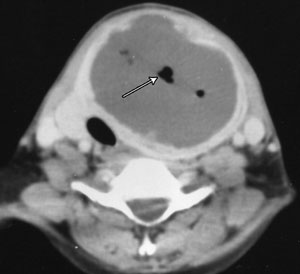

A 40-year-old woman presented with sudden onset of a painful neck swelling, fever and dysphagia. Examination revealed a warm, tender lump in her thyroid gland. Five weeks previously, she had had an abdominal hysterectomy with bilateral salpingo-oophorectomy for pelvic inflammatory disease. There was no evidence of leukopenia or diabetes. Computed tomography and x-ray images were consistent with a diagnosis of thyroid abscess (Figure 1 and Figure 2).